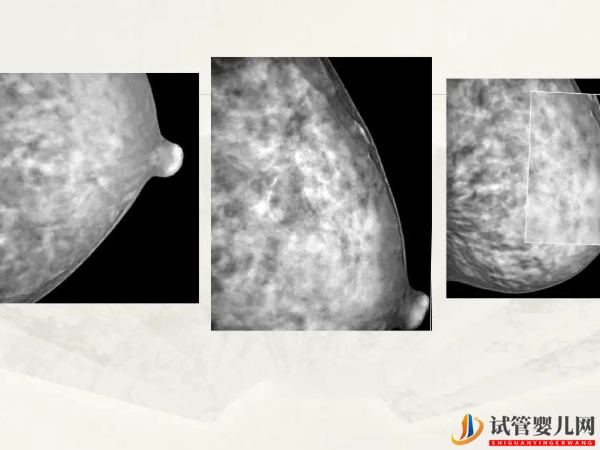

乳腺B超就是通过B超来检查乳房处的疾病,这是乳房检查中的常用的方式,它属于无创的检查技术,对于常见的乳腺增生、乳腺纤维瘤、乳腺癌等都是有帮助诊断的价值。做乳腺B超前不用做特殊的准备工作,到医院后随时都可以做。

做试管婴儿期间检查乳腺是为了及早发现并治疗乳腺增生和乳腺癌等疾病,如果确实存在异常,那么在治疗之后保证身体健康的情况下再做试管婴儿。而乳腺B超是女性健康检查中重要的检查之一,可以发现多钟疾病,比如: